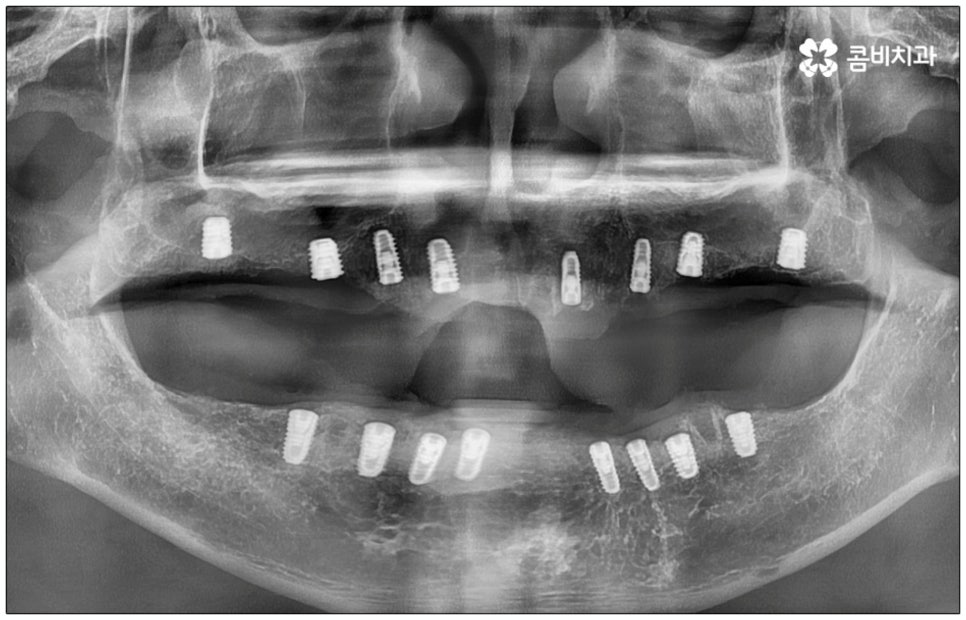

전신 질환을 앓고 있는 분들이나 고령의 환자분들, 다수의 임플란트가 필요한 분들의 경우 컴퓨터 분석을 활용한 임플란트 방식을 통해 도움받아 볼 수 있는데요. 네비게이션 임플란트라고 불리는 이 방식은 첨단 장비를 통해 육안으로 확인하기 어려운 구강 내부의 골조직, 신경 등의 해부학적 구조를 살펴본 다음 3D 모의 수술을 통해 최적의 수술 경로를 찾아내어 가이드를 제작하고 이를 장착하여 그대로 진행하기 때문에 보다 정확하고 안전하게 노인임플란트 수술을 진행할 수 있습니다.

이러한 네비게이션 임플란트 방식은 디지털 기술로 위험 요소를 사전 분석하여 식립 위치와 각도를 보다 정교하게 예측하기 때문에 임플란트 부작용의 발생률을 낮추고 식립 안정성을 높일 수 있는데요. 무절개 또는 최소절개 수술이기 때문에 시술 시간이 짧고 통증이 적으며 회복 기간이 빠르다는 장점을 가지고 있으나 정밀 검진 후 상황상 골유착 과정의 안정성이 떨어질 수 있는 케이스의 경우에는 절개 및 개방 후 수술을 진행하는 것이 좀 더 유리하기 때문에 꼼꼼한 검진, 정확한 판단, 의료진의 높은 숙련도가 굉장히 중요하다고 할 수 있어요.

특히 다수의 치아를 상실했을 때 전체적인 교합, 골조직 및 잇몸 상태, 얼굴형과의 조화 등 모든 부분을 종합적으로 고려하여야 하며 노인임플란트 수술의 경우 다양한 변수가 발생할 수 있기 때문에 이러한 고난도 임플란트 케이스에 노련하게 대처할 수 있도록 풍부한 임상 경험과 노하우를 갖춘 의료진인지, 정밀 검진 기계를 보유하고 있는지, 처음부터 끝까지 철저한 케어 시스템을 갖추고 사후 관리까지 꼼꼼하게 진행하는지 등을 잘 살펴보시고 임플란트 수술을 진행할 치과를 신중하게 선택하시길 권유드리고 있습니다.